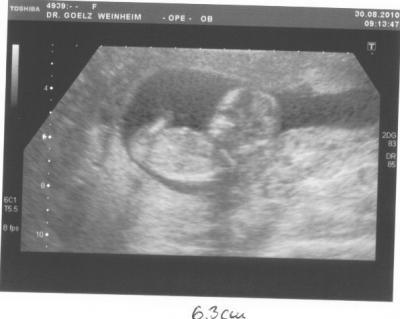

Hallo, an alle! ... Hatte heute morgen meine FA Termin zur NFM und Bluthormone usw. also das soganannte Ersttrimester-Screening! Hab alles schön über mich ergehen lassen, Blutabnahme... da hat sie schön zart gestochen, dann Pflaster drauf und gut. Hab warscheinlich nicht genug drauf gedrückt, denn estwas später war mein ganzer Arm, inkl. Pulloverarm blutig. Iiiihhh, was für eine Sauerei. Hab dann nen Druckverband bekommen. Ab das Baby TV- war toll. Man hat der krümel gezappelt. Mein FA hat tatsächlich fast 15 min gebraucht um die Nackfalte darzustellen und auszumessen. War alles in Ordnung, nicht verdickt, ca. 1.1mm stark. Na das hört sich doch gut an, oder?Mein Krümel ist satte 6,3cm groß und hat sogar schon gegähnt. Hihi! Hab acuh ein schönes Bildchen, und in 3 Wochen darf ich schon wieder kommen. Dann könnte se ein Outing geben. So, und da ich nun auf der sicheren Seite schwimme, denn ich bin nun in der 13.SSW bin auch irgendwie gelöster und unser Projekt neues Kinderzimmer kann starten! Ich grüße euch alle und habt eine schöne Woche, LG, Manu.